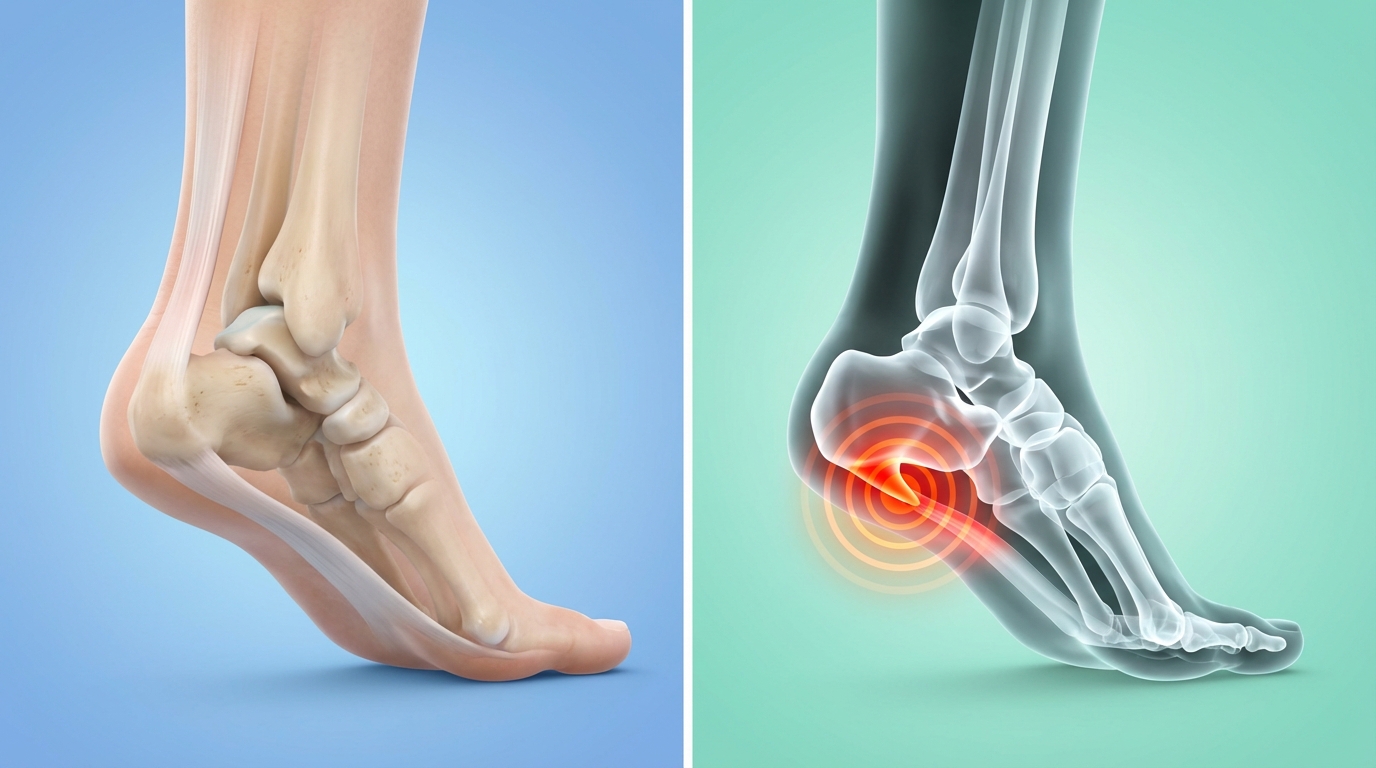

Po kilku tygodniach nie wytrzymałem i poszedłem do ortopedy.

Rentgen, USG, test ciśnieniowy.

Diagnoza była jednoznaczna: ostroga piętowa i podrażnienie powięzi podeszwowej.

Pod stopą znajduje się mocna płytka ścięgna, czyli powięź podeszwowa.

Przy każdym kroku napina się ona jak lina między piętą a palcami.

to przy każdym kroku dochodzi do przeciążenia tego przyczepu ścięgna w pięcie.

Organizm reaguje:

niewielkimi pęknięciami

zapaleniem

i w pewnym momencie ewentualnie wyrostkiem kostnym, znanym jako „ostroga”.